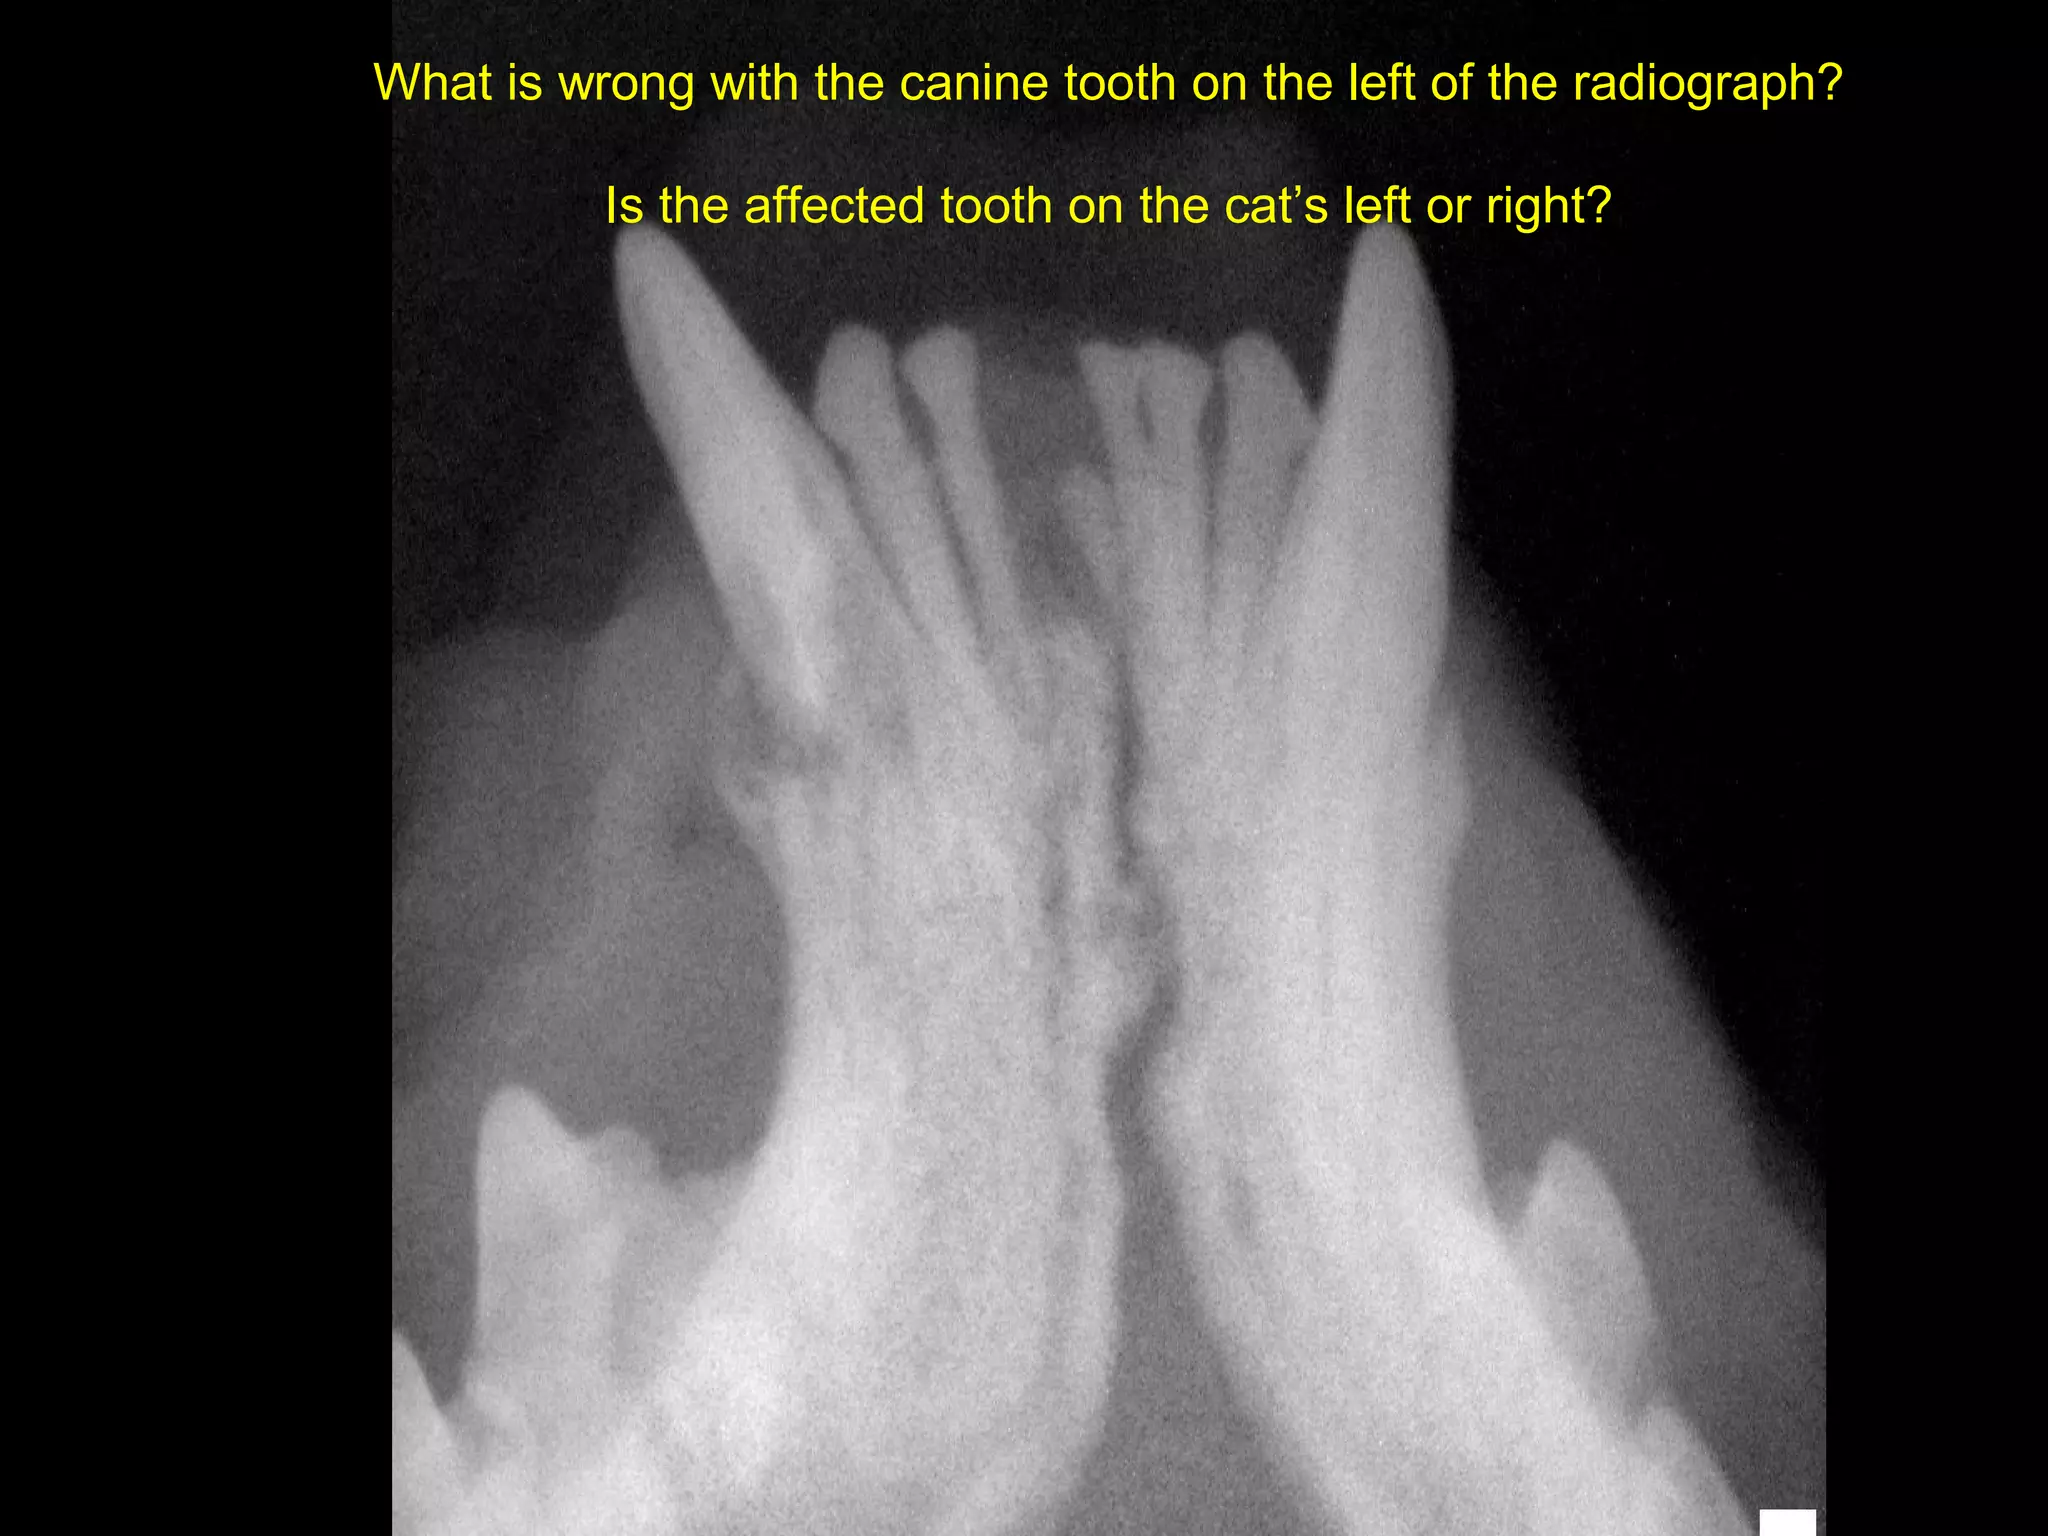

What is wrong with the canine tooth on the left of the radiograph?

Is the affected tooth on the cat’s left or right?

What is wrongwith the canine tooth on the left of the radiograph? Is the affected tooth on the cat’s left or right? 18